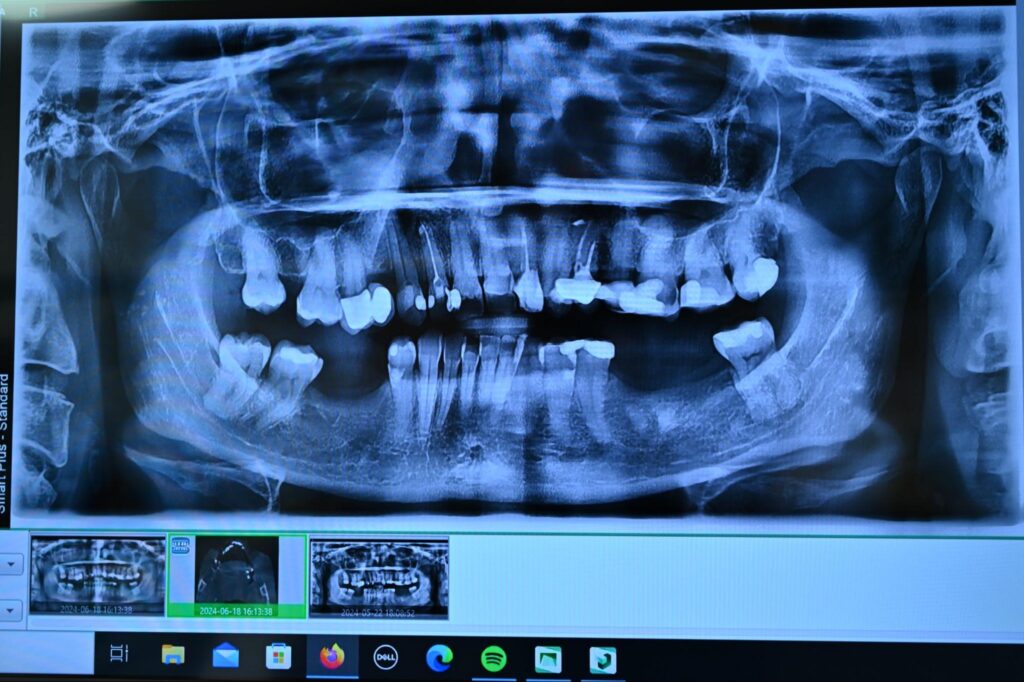

Zdjęcie panoramiczne (pantomogram) to podstawowe badanie obrazujące całą jamę ustną na jednym obrazie. Pokazuje wszystkie zęby, kości szczęk, zatoki szczękowe i stawy skroniowo-żuchwowe.

Pantomogram ujawnia problemy niewidoczne podczas zwykłego przeglądu: próchnicę pod wypełnieniami, stany zapalne przy korzeniach, zęby zatrzymane, torbiele, zanik kości. To narzędzie niezbędne w diagnostyce przed leczeniem ortodontycznym, protetycznym czy implantologicznym.

Panoramiczne zdjęcie rentgenowskie jamy ustnej z widocznością zębów i struktur kostnych